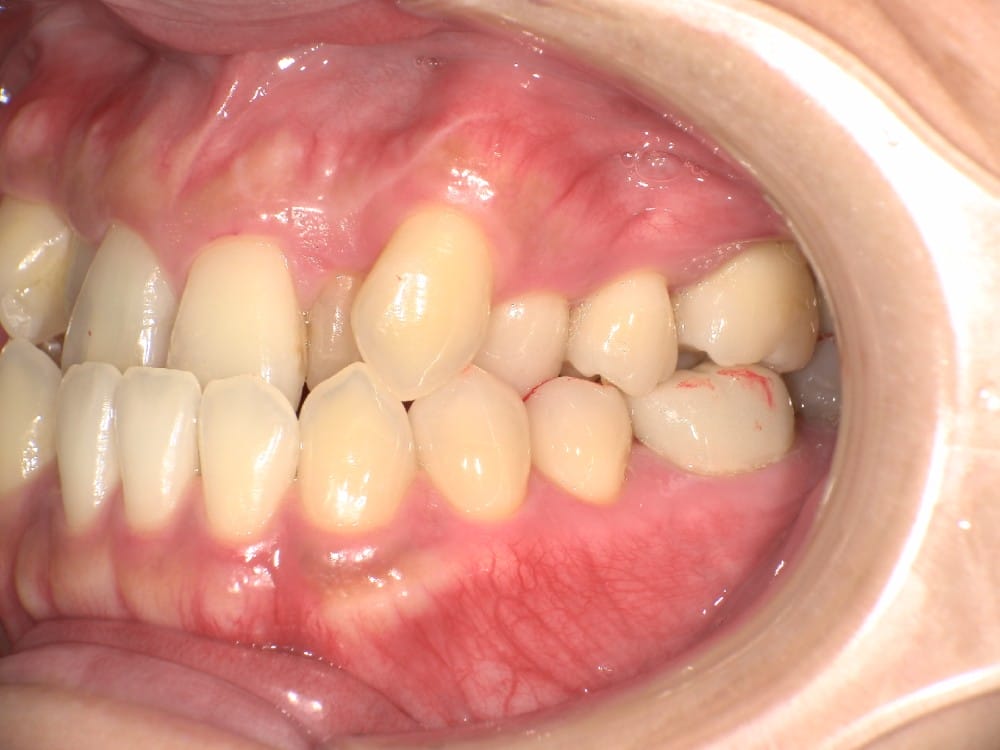

30代の女性で、受け口とガタガタを主訴にご来院されました。

治療前

分析しますと

- 骨格的な上下あごの前後差は中等度〜重度

- 噛み合わせの位置も下あごの奥歯が半分くらい前にズレていた

- 上の前歯が内側に傾斜している

というケースで、外科的な処置も検討するようなケースでした。

骨格的なズレや奥歯の噛み合わせのズレもあり、重度の受け口でしたが、上あごの前歯が内側に傾斜しているため、本来の歯の軸に戻すことで、受け口を改善できると診断し、治療を開始しました。

先ほどのケースと同じように、患者さまに外科的な手術の選択肢も提示しましたが、希望されず、横顔の変化はおそらく起こらないことを納得の上、治療をスタートいたしました。

今回のケースも奥歯の移動量が大きいため、マウスピースだけでは難しいと判断し、カリエールとよばれる装置を補助的に使用し、上下の噛み合わせの前後関係を整えることで、手術を行わずに機能面と見た目の両方が改善することにしました。